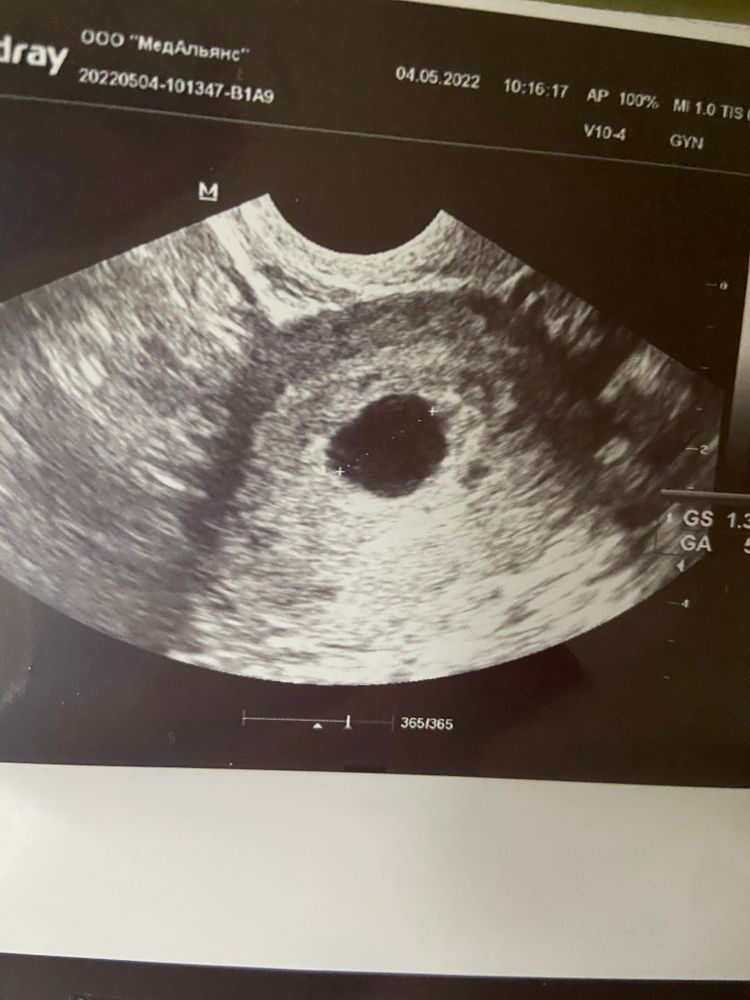

Анэмбриония

До этого делали УЗИ? Просто для ПЯ 14 мм ещё слишком мало, чтобы судить об анэмбрионии. Поэтому вопрос что было в предыдущих УЗИ.

Нина, 20 апреля узи ПЯ 7мм сегодня ПЯ 14мм внутри пусто овуляцию я не отслеживала и в последнее время цикл был с перебоями

Девочки, зашла отписаться. Неделю назад делаю УЗИ. ПЯ 17 мм, желточный мешочек 1.7 мм. Срок по М 6.5 недель. Врач ставить анэмбрионию, в заключении пишет замершая. Я в шоке. Развернула монитор, говорит видите пусто. Иду домой, читаю. Изучаю все. Итак, такой диагноз ставят при ПЯ больше 25 мм, и по УЗИ. В течении двух недель после появления плодного яйца должен появиться желточный мешочек. Если он есть, но нет эмбриона, то ждать ещё 11 дней. Это из литературы. Читаю, что девочкам находили и в 9 недель. Жду ровно неделю. Иду к другому врачу в платное отделение род дома на хороший аппарат, и вуаля. Эмбрион 9, 4 мм. Это за неделю. Вырасти он так не мог. Врач сказал, на этом сроке он плоский и может прилипнуть к яйцу. Счастья не было предела.